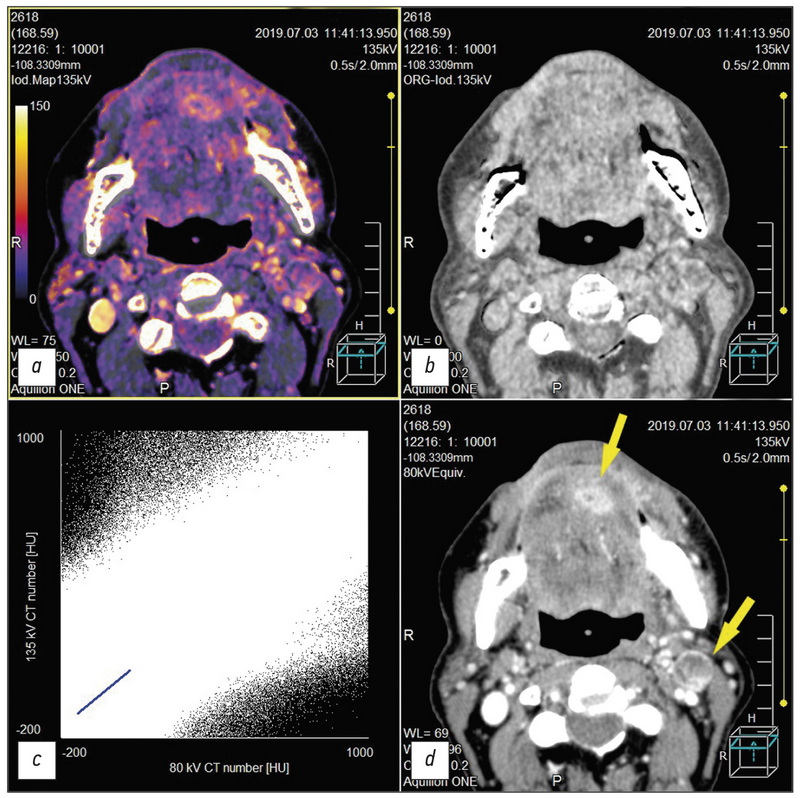

This study reviewed the head and neck cancer diagnosis publications using dual-energy computed tomography (DECT). The qualitative and quantitative analysis of the data was DECT obtained using intravenous contrast enhancement for localized tumors, which shows the importance of constructing iodine maps for obtaining additional diagnostic information. Including the article is described aspects of improving visualization of the oropharyngeal region against the background of artifacts from dental implants. Several research articles highlight the current state of the issue and the role of post-processing of “raw data” DECT, obtaining a range of monochromatic images of a tumor and other pathological changes in the head and neck region in the article. Several learned treatises were also reflected. DECT with intravenous contrast enhancement and routine computed tomography to reduce radiation exposure to patients were compared particularly due to the possibility of obtaining virtual native diagnostic images from a contrasting series of DECT volumes during post-processing. In addition, this review also includes references to works that highlight the development of DECT as the method. Finally, the physical principles underlying DECT and the prospects for the development of the method are briefly represented.